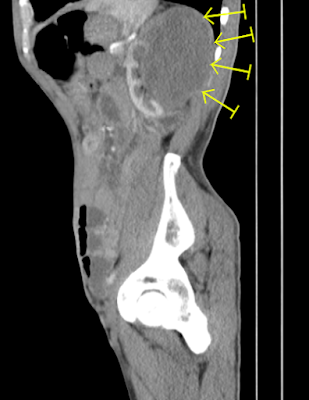

• About 76x74mm large hypodense mass lesion is seen in the left kidney showing inhomogeneous enhancement and closely located with psoas muscle.